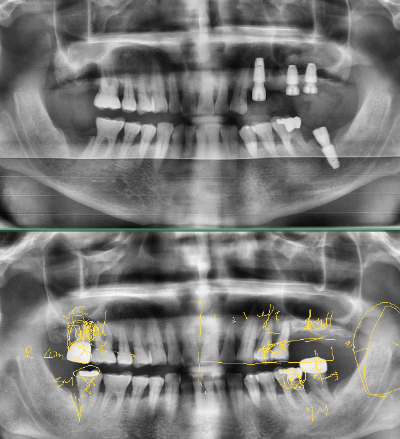

위에서 부터 환자의 수술 후, 전 파노라마 방사선 사진, 아래는 설명한 흔적이 남아있습니다.

이번 수술은 세 개를 발치하고 네 개를 식립 하는 케이스였습니다.

환자의 수술 부위의 단면이 캡처된 CT가 컴퓨터 화면에 띄워져 있고.. 수술용 고성능 하이피스에 엔진이 돕니다. '히잉~'